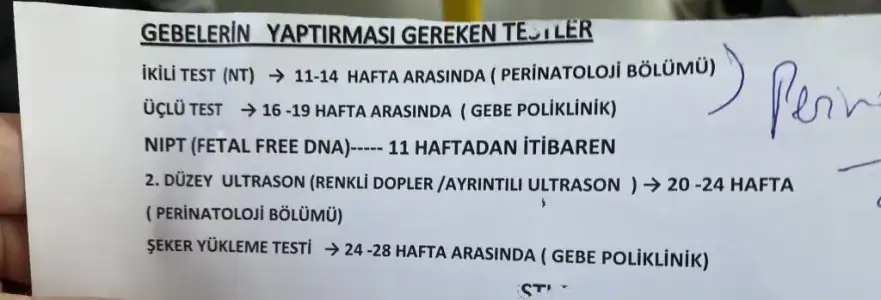

Bulantı için ilaç yazdı. 2-3 hafta sonra gel tekrar dedi. Yapılacak testler için form doldurdum. Kağıt verdi vs. Bizden haberler